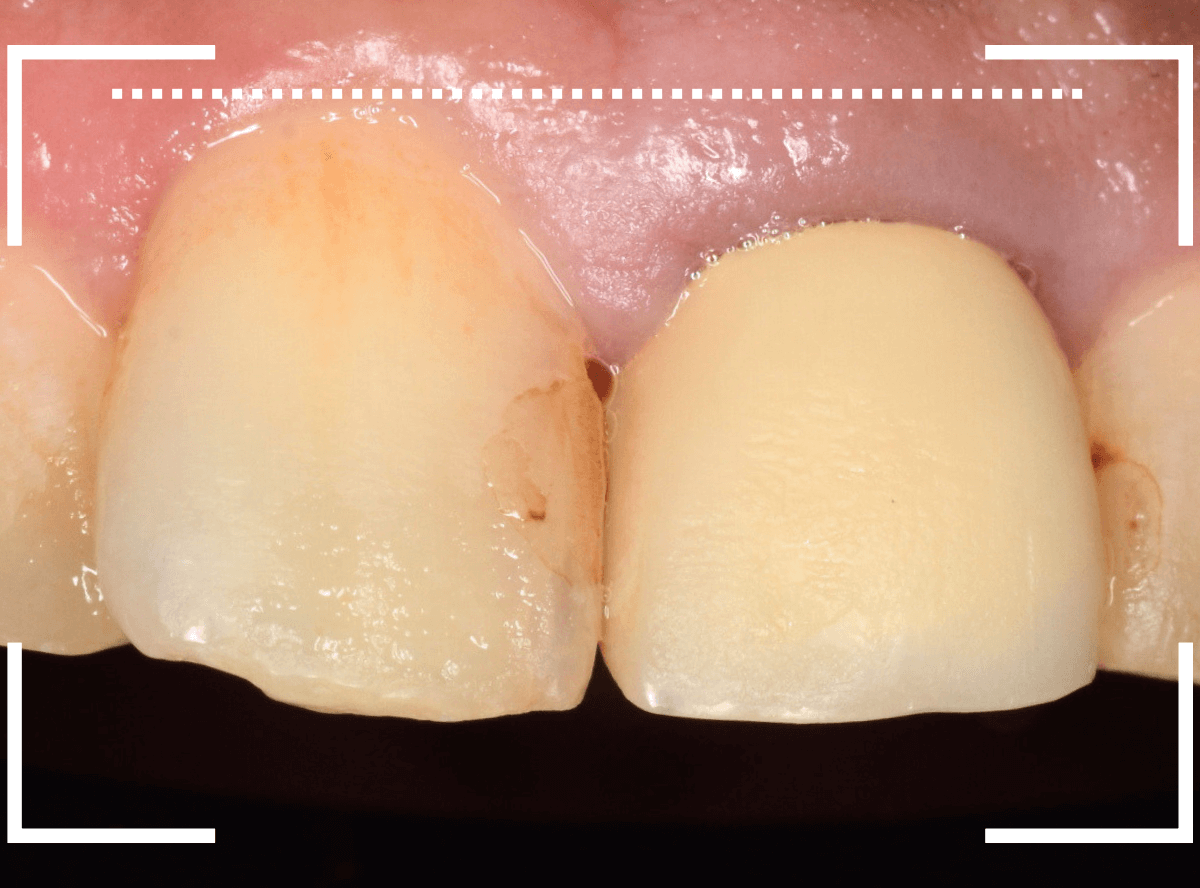

以前に治療した上のさし歯を綺麗にやり直したいというご相談の患者さんです。

保険診療で行うさし歯「レジン前装冠」が入っています。

「レジン前装冠」は裏から撮影した写真を見ていただければわかるように、銀歯の上にレジン(プラスチック)を盛ったさし歯で、実質的には銀歯です。

銀歯の上にプラスチックを盛るために、歯をかなり大きく削る必要があったり、短期間で劣化・変色する(この方の差し歯も劣化してのっぺりした黄土色になっています)、金属の色素が歯肉に溶け出して歯肉が黒くなる(メタル・タトゥー)などのデメリットがあります。

さて、この方の歯の形を確認すると、左右でかなり歯の長さに差があります。